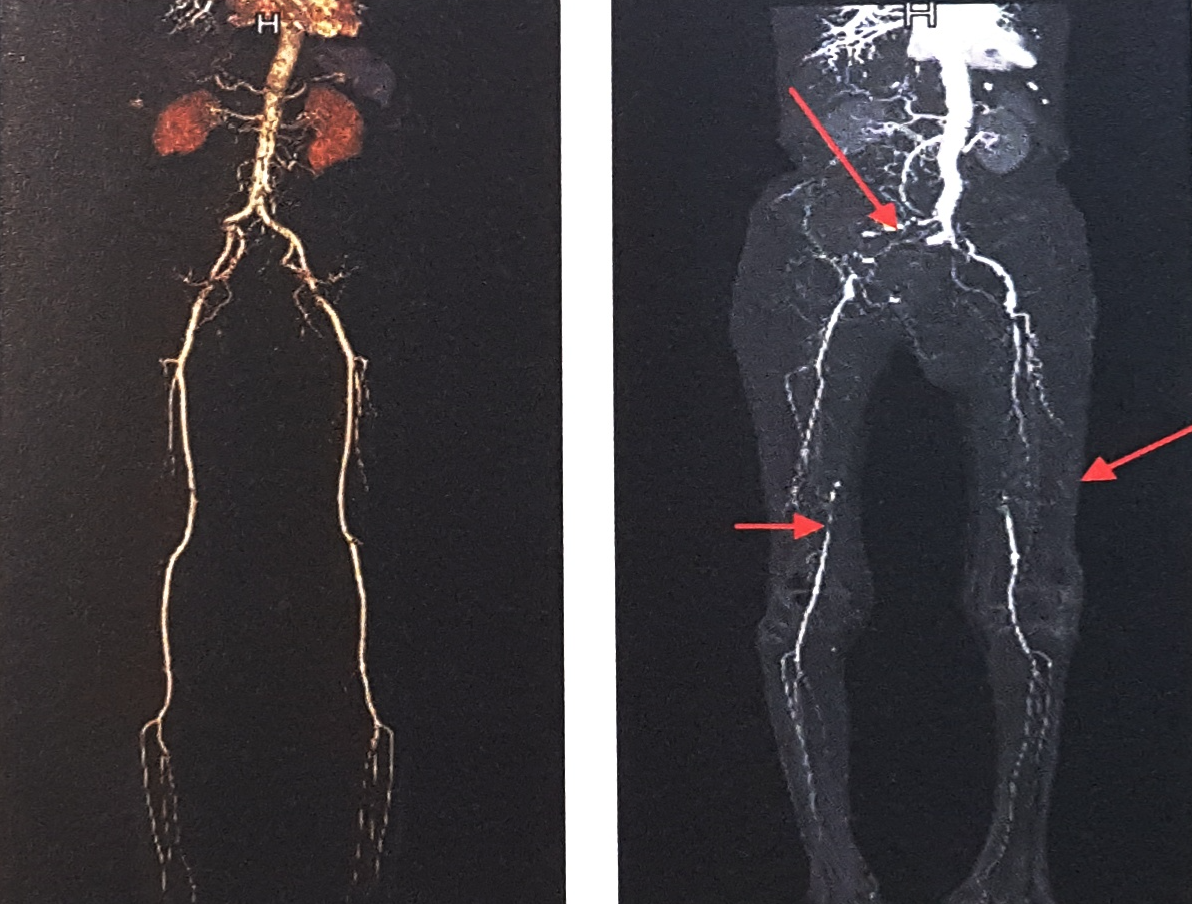

CT촬영 종류에는 동맥 및 정맥 혈관 CT, 복부대동맥 CT, 심부정맥혈전 & 폐동맥 CT, 관상동맥 CT 등이 있습니다. 혈관질환의 정확한 검사 및 진단을 위해서는 혈관외과 전문의의 적절한 처방을 받아야 합니다.확인하고자 하는 대상에 따라서 촬영방법이 조금씩 차이가 있으나 기본적으로는 모두 같은 검사방법입니다.

대동맥부터 다리 전체의 동맥

다리의 무릎아래 동맥